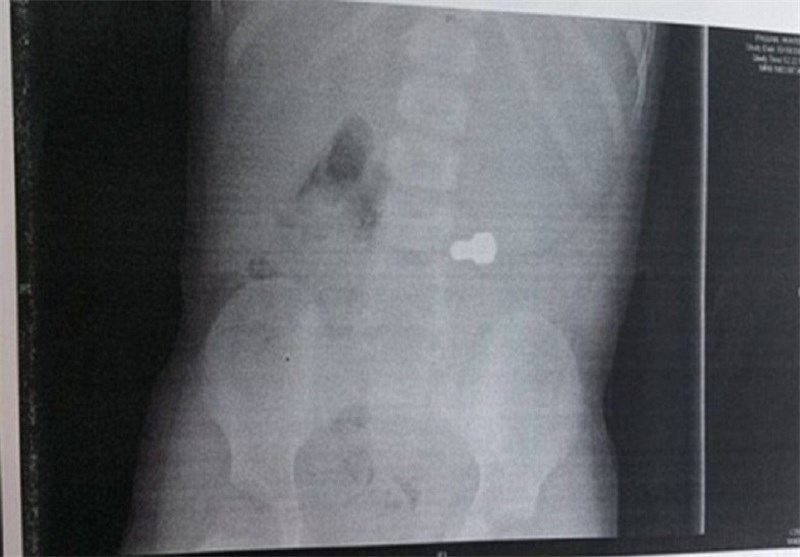

تصاویر عکسبرداری در بیمارستان، این قطعه پیچ بزرگ را نشان میدهد.